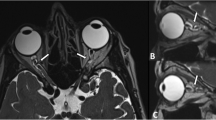

Fifty-six patients (112 eyes) (age 65 years-old [range 26–88]; 70% male) had isolated bilateral glaucoma with at least one-eye MRI optic nerve abnormality. The indication for MRI was atypical/asymmetric glaucoma in 91% of patients. Of the 112 eyes, 23 had optic nerve T2-hyperintensity alone; 33 had both optic nerve T2-hyperintensity and MRI optic nerve atrophy; 34 had MRI optic nerve atrophy alone; and 22 did not have abnormal optic nerve MRI-findings. None had optic nerve enhancement. A statistically significant association between optic nerve T2-hyperintensity or MRI optic nerve atrophy and glaucoma severity parameters was found.